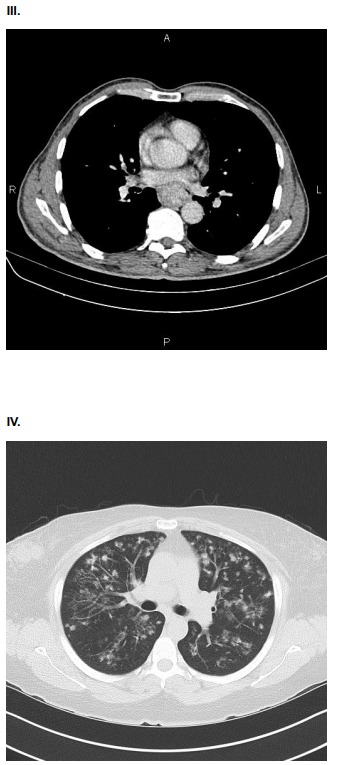

3834589 Ano: 2024

Disciplina: Medicina

Banca: HL

Orgão: Pref. Iturama-MG

Provas:

AMV, 75 anos, tabagista, com queixa de dor torácica súbito, do tipo lancinante. Ao exame físico: Regular estado geral. ACV: RCR em 2T, pulsos radiais assimétricos. PA: 150x80 mmHg. FC 110. Sat O2 90%. Solicitado ECG e Tomografia de Tórax e Abdome com contraste.

Assinale a alternativa que contenha o achado compatível com o quadro clínico da paciente.